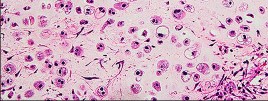

Figures 7a through 7d are the radiograph, MR images, and biopsy specimen of a 35-year-old man who has a painful, slowly enlarging knee mass. Which chromosomal translocation is characteristic of this pathology?

Synovial sarcoma is a soft-tissue sarcoma that usually occurs in young adults. Synovial sarcoma often causes pain, unlike most soft-tissue sarcomas, which generally do not cause pain. Imaging characteristics include soft-tissue calcifications on plain radiographs and a heterogeneous mass that is generally isointense to muscle on T1-weighted images and hyperintense to muscle on T2-weighted images. There are biphasic and monophasic types of synovial sarcoma. The biphasic

type, which is depicted here, has both spindle cell and epithelial components and will stain for both vimentin and cytokeratin. More than 90% of patients with synovial sarcoma have a characteristic genetic translocation of t(X;18), which results in the fusion protein SS18-SSX. This translocation can be stained for use of florescence in situ hybridization technology. t(11;12) is seen in Ewing sarcoma. T(9;22) is seen in extraskeletal myxoid chondrosarcoma. t(12;16) is seen in myxoid liposarcoma.